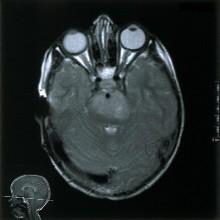

N.A.: Imaginea prezinta cazul unui pacient de 5 ani cu gliom al trunchiului cerebral, evaluat cu ajutorul rezonantei magnetice nucleare.